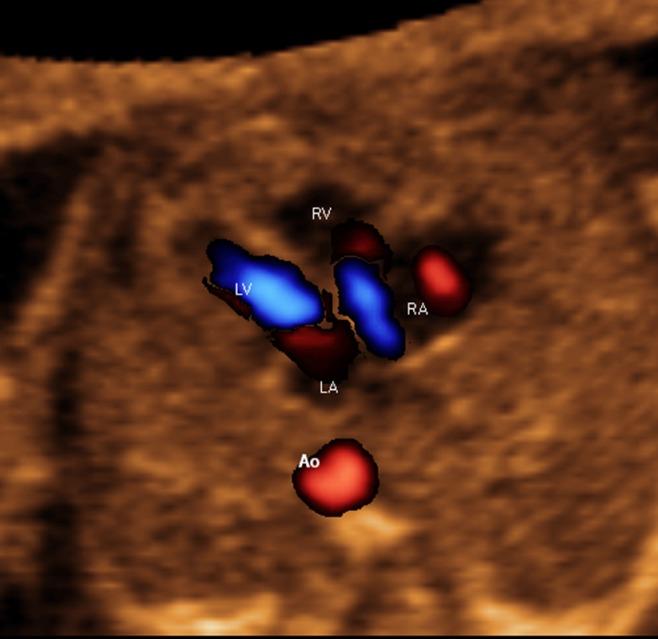

A prospective cohort study was conducted of fetuses in the second and third trimesters with a normal heart or with congenital heart disease (CHD). One or more spatiotemporal image correlation (STIC) volume datasets, combined with color or bidirectional power Doppler (S-flow) imaging, were acquired in the apical four-chamber view. Each successfully obtained STIC volume was evaluated by STICLoop™ to determine its appropriateness before applying the FINE method. Visualization rates for standard fetal echocardiography views using diagnostic planes and/or Virtual Intelligent Sonographer Assistance (VIS-Assistance®) were calculated for grayscale (removal of Doppler signal), color Doppler and S-flow Doppler. In four cases with CHD (one case each of tetralogy of Fallot, hypoplastic left heart and coarctation of the aorta, interrupted inferior vena cava with azygos vein continuation and asplenia, and coarctation of the aorta with tricuspid regurgitation and hydrops), the diagnostic potential of this new technology was presented.

A total of 169 STIC volume datasets of the normal fetal heart (color Doppler, n = 78; S-flow Doppler, n = 91) were obtained from 37 patients. Only a single STIC volume of color Doppler and/or a single volume of S-flow Doppler per patient were analyzed using FINE. Therefore, 60 STIC volumes (color Doppler, n = 27; S-flow Doppler, n = 33) comprised the final study group. Median gestational age at sonographic examination was 23 (interquartile range, 21-27.5) weeks. Color Doppler FINE generated nine fetal echocardiography views (grayscale) using (1) diagnostic planes in 73-100% of cases, (2) VIS-Assistance in 100% of cases, and (3) a combination of diagnostic planes and/or VIS-Assistance in 100% of cases. The rate of generating successfully eight fetal echocardiography views with appropriate color and S-flow Doppler information was 89-100% and 91-100% of cases, respectively, using a combination of diagnostic planes and/or VIS-Assistance. However, the success rate for the ninth echocardiography view (i.e. superior and inferior venae cavae) was 33% and 30% for color and S-flow Doppler, respectively. In all four cases of CHD, color Doppler FINE demonstrated evidence of abnormal fetal cardiac anatomy and/or hemodynamic flow.

The FINE method applied to STIC volumes of normal fetal hearts acquired with color or bidirectional power Doppler information can generate successfully eight to nine standard fetal echocardiography views (via grayscale, color Doppler or power Doppler) in the second and third trimesters. In cases of CHD, color Doppler FINE demonstrates successfully abnormal anatomy and/or Doppler flow characteristics. Published 2017. This article is a U.S. Government work and is in the public domain in the USA. Ultrasound in Obstetrics & Gynecology published by John Wiley & Sons Ltd on behalf of the International Society of Ultrasound in Obstetrics and Gynecology.